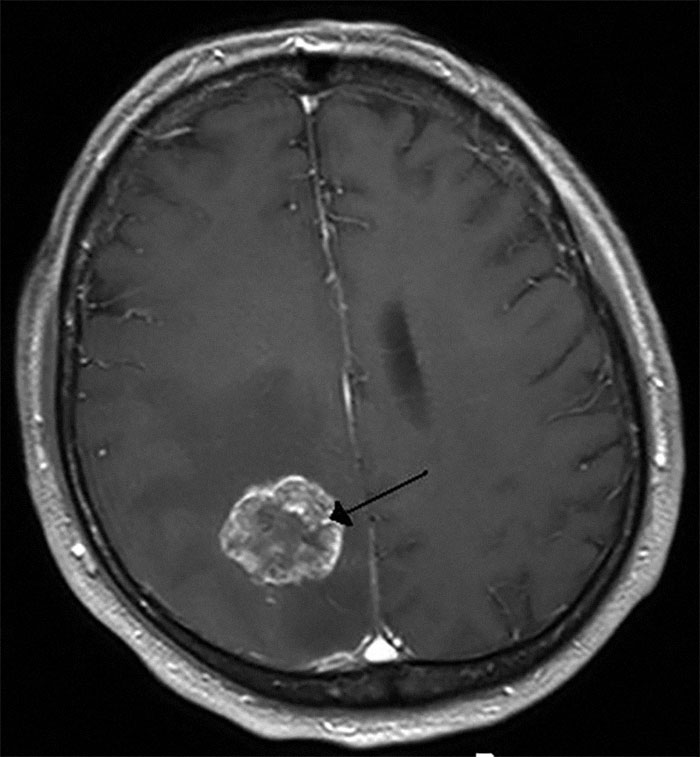

One guy who had been stabbed through the heart with a steak knife by his wife was in peak physical shape, but when the pathologist pulled his brain out he said "look at this". I have no biology training, but the golf ball sized tumor on his brainstem was obvious even to me. Doctor said he had maybe 90 days to live at the time of his death.

The wife went to prison for murder, and all she had to do was wait a few months and she'd have been a hero Army widow.

Image credits: Underwater_Karma